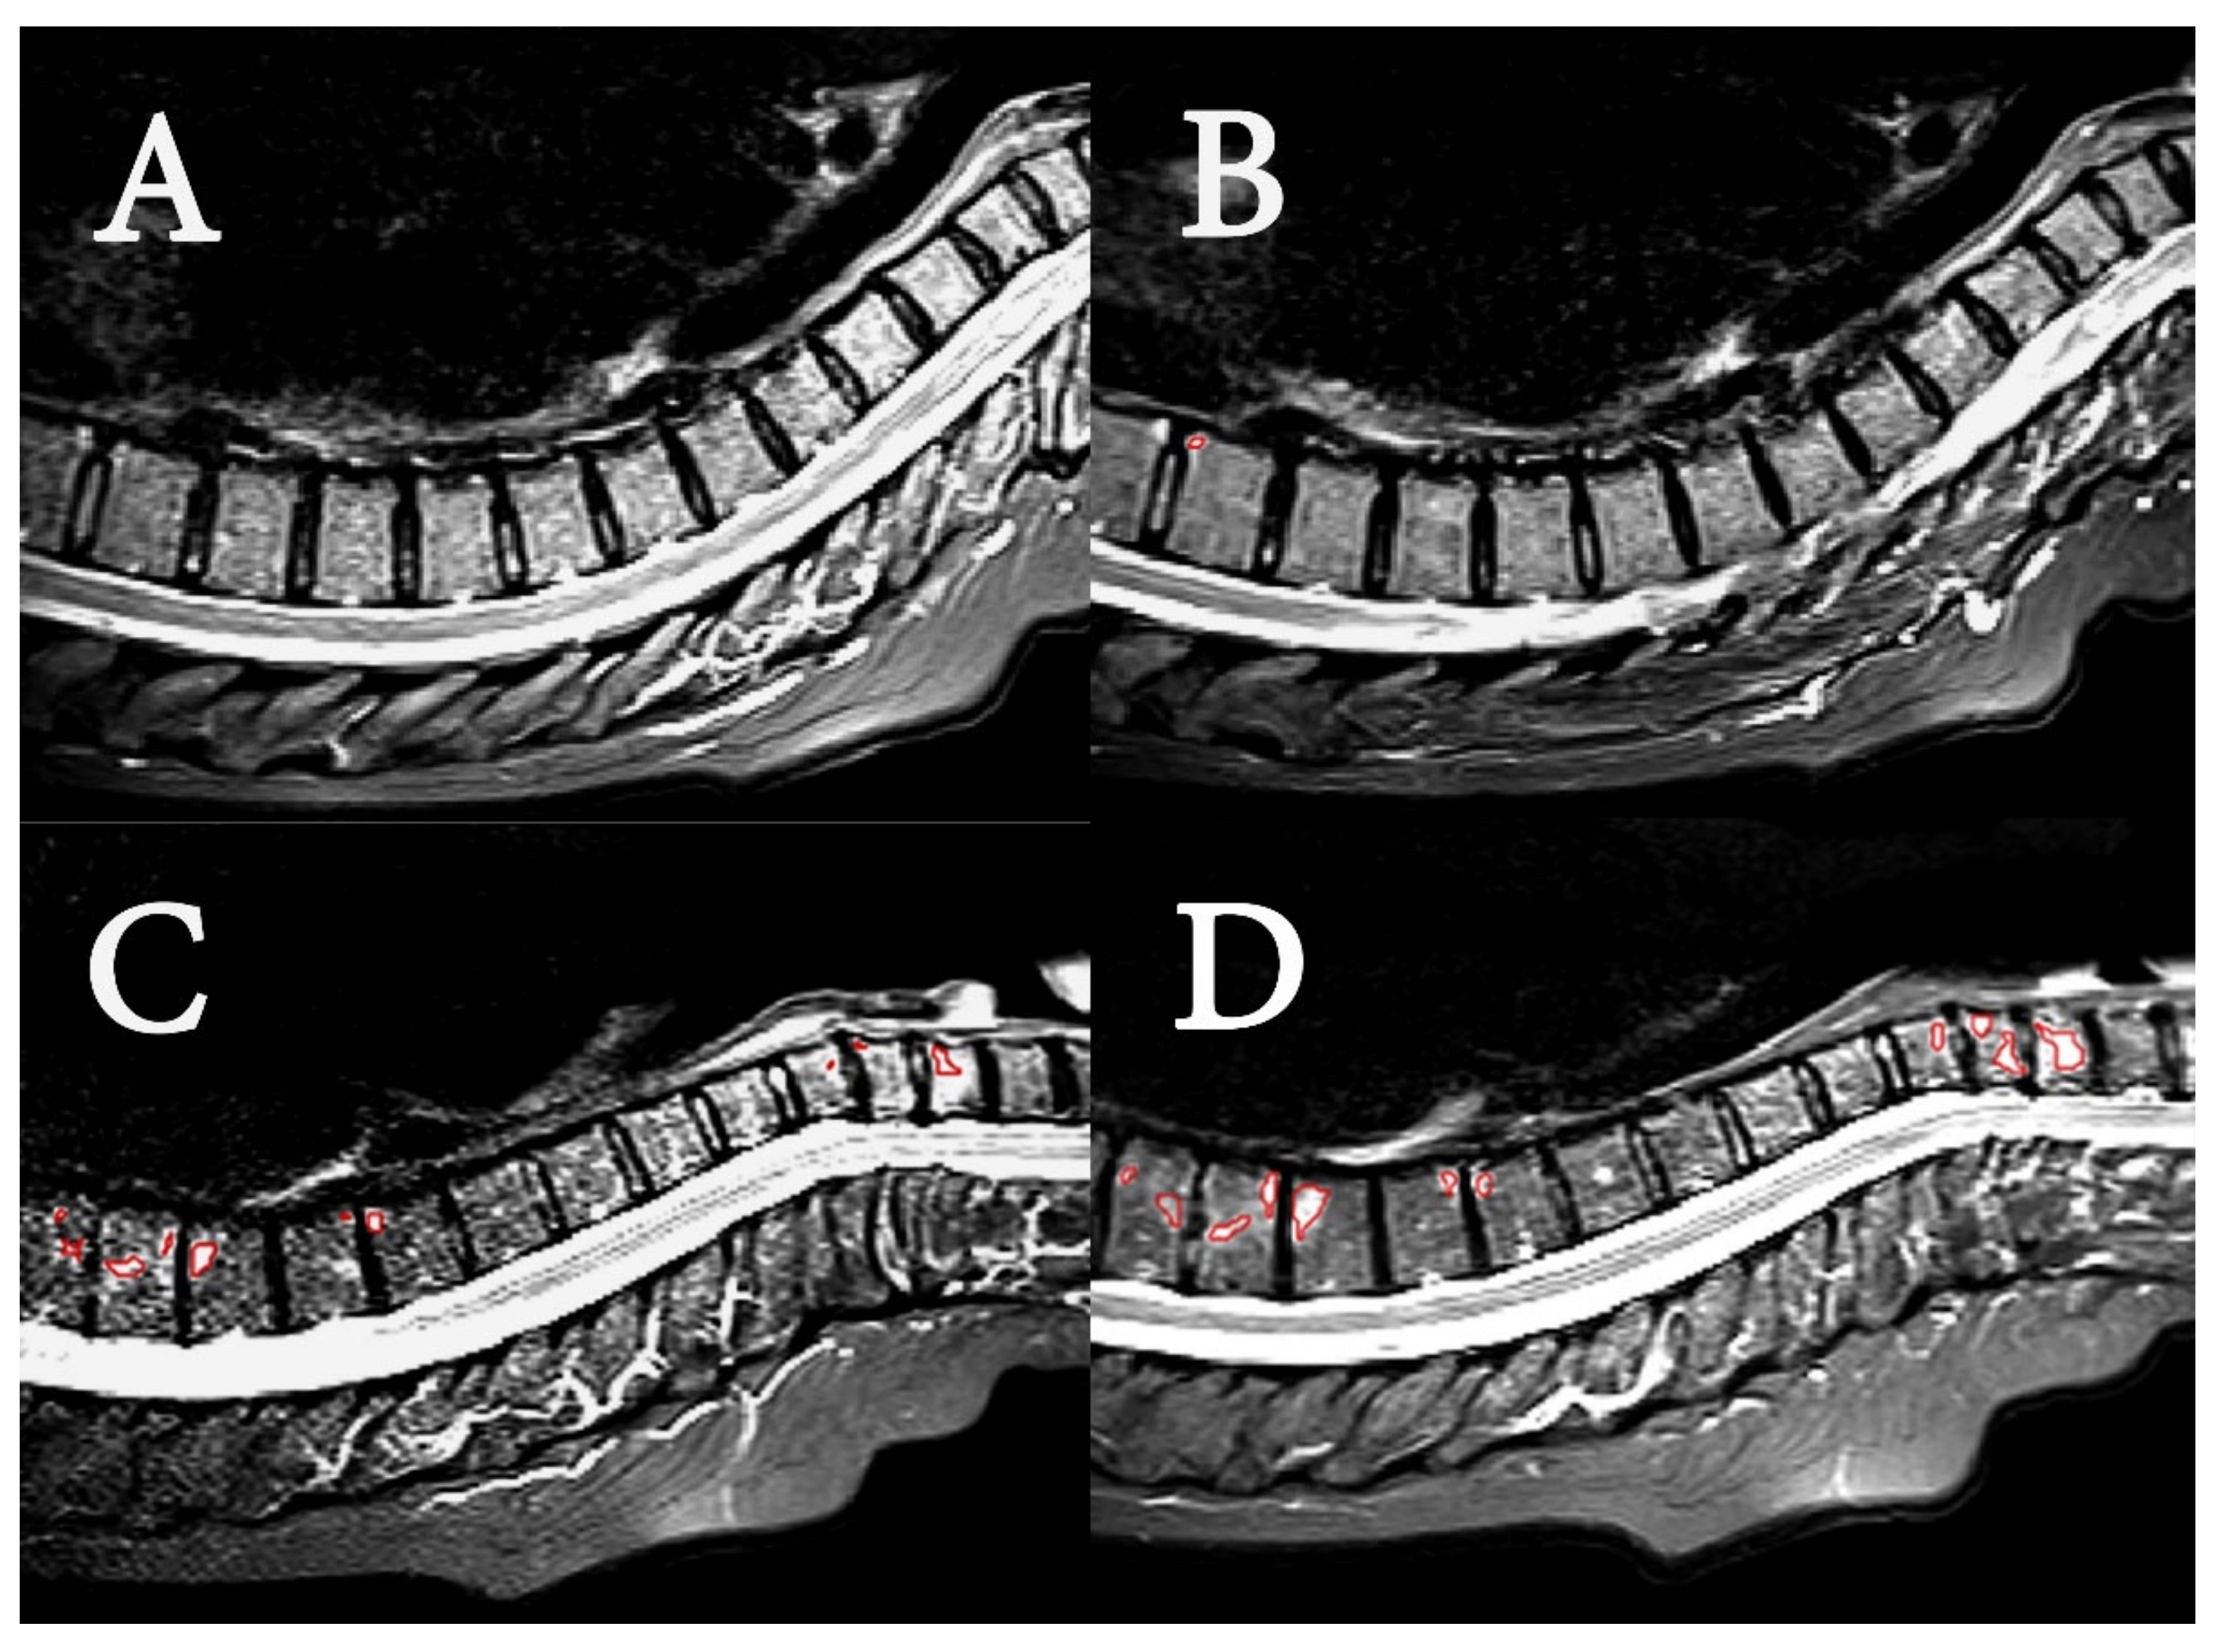

Examples of acquired MR images are shown in Figure 2, demonstrating the PsA lesions of two patients with low and high disease burden. MR images of the spine from 21 of 37 patients were found negative with respect to BME in the radiological evaluation at both timepoints. Sixteen patients (43%) were identified with BME, consistent with axial manifestation of PsA. The radiologically manifested axial PsA was considered mild to moderate for both groups, and disease burden in terms of BME was stable. The findings are summarized in Table 2. The number of patients with changes of BME after 11 weeks was not significantly different between the HIIT and control group (p-value: 0.50).

Figure 2.

MR image examples. Sagittal short tau inversion recovery (STIR) MR images of upper spine in two patients. (A) (baseline) and (B) (11 weeks) are of a patient with low SPARCC scores (4 and 2, respectively). The images show the spine from the second cervical vertebrae (C2) to thoracic vertebrae 12 (TH12). Segmented region in red in B shows minor BME in corner of TH10. (C) (baseline) and (D) (11 weeks) are of patient with high SPARCC scores (39 and 50, respectively). The images show the spine from the second cervical vertebrae (C2) to thoracic vertebrae 11 (TH11), and segmented regions in red in (C) and (D) show BME in C5 to C7, and in TH5 to TH9.